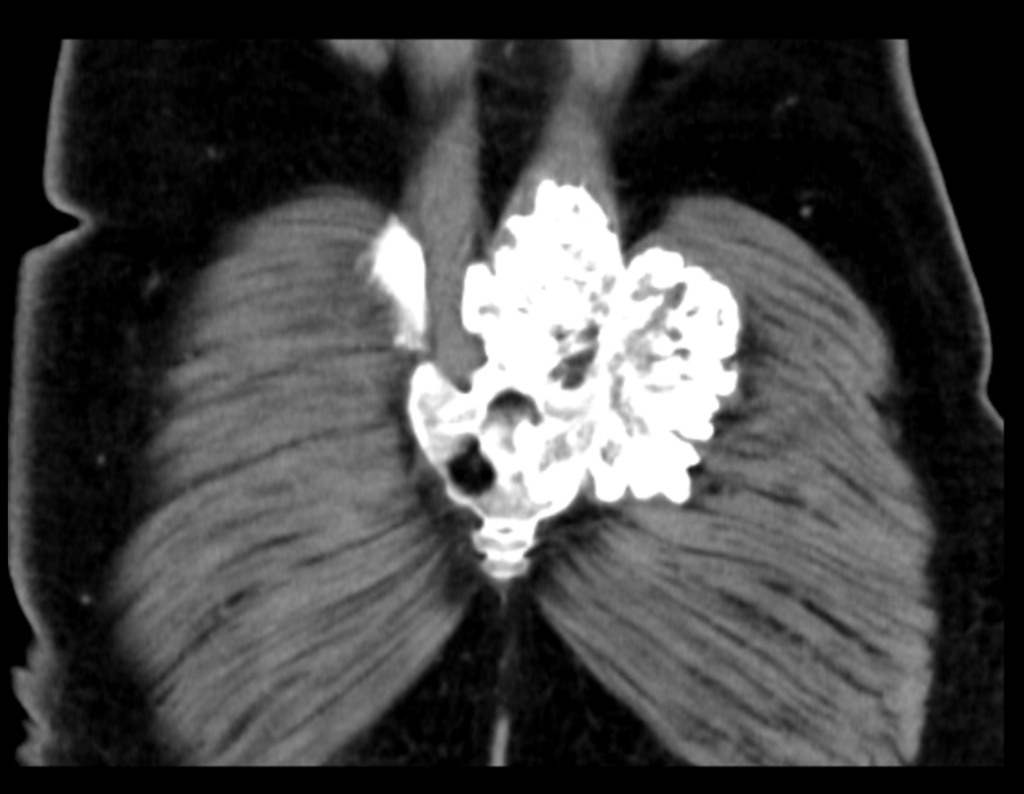

Reconstrução 3D em TC: As imagens em 3D da bacia em diversas posições mostraram a extensão e localização da lesão, afetando o processo espinhoso de S2 e a região posterior do ilíaco esquerdo. O comprometimento das lâminas e do processo espinhoso de S3 e da região sacro-ilíaca foi claramente visualizado.

Imediato: No pós-operatório imediato, o paciente foi monitorado com imagens de TC em 3D para avaliar a eficácia da ressecção e verificar a ausência de lesões residuais. A recuperação inicial mostrou boa resposta ao tratamento, com controle adequado dos sintomas e complicações mínimas.